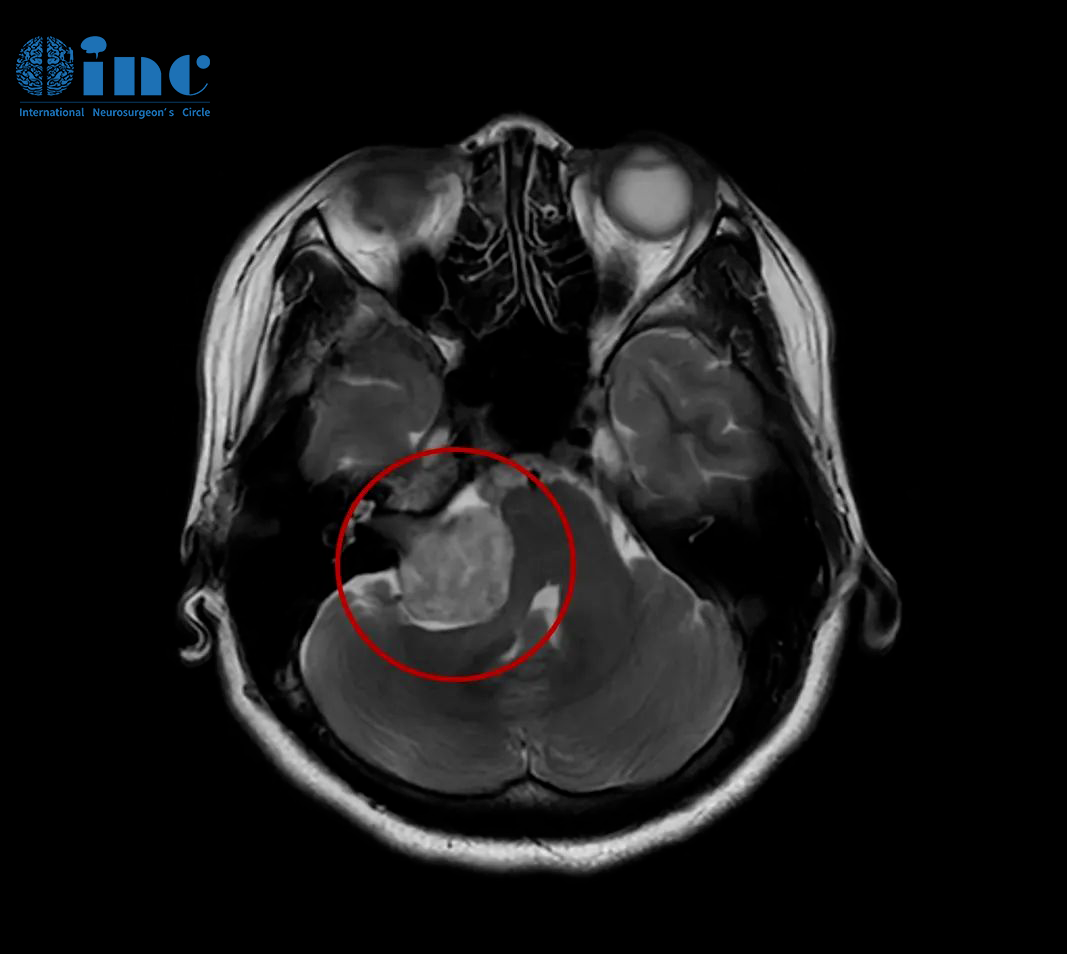

2019年,INC德国巴特朗菲教授曾4次来华,并在国内协作的三甲医院(苏州大学附属第一医院、苏州大学附属儿童医院、浙江大学医学院附属邵逸夫医院、无锡市第二人民医院等)开展疑难手术示范等,成功展示了多例在脑干、颅底、功能区等复杂病变(包括脑肿瘤/脑海绵状血管瘤/脑血管病变等)的全切及近全切手术之作。INC巴教授2019来华疑难手术示范掠影

2021巴教授来华疑难手术示范掠影2022作为江苏省卫生支撑计划中德国际合作交流项目,INC国际神经外科医生集团旗下组织世界神经外科顾问团(WANG)成员、世界神经外科联合会WFNS教育委员会主席、德国INI国际神经学研究所Helmut Bertalanffy(汉莫特·巴特朗菲)教授受邀再次来华学术交流及疑难手术示范。在INC合作的国内三甲医院——苏州大学附属儿童医院及苏州独墅湖医院,巴特朗菲教授与国内专家同台示范手术,在救治疑难病症患者的同时,切磋手术技巧、学术交流讲学,推进中外神经外科之间的良性互动。